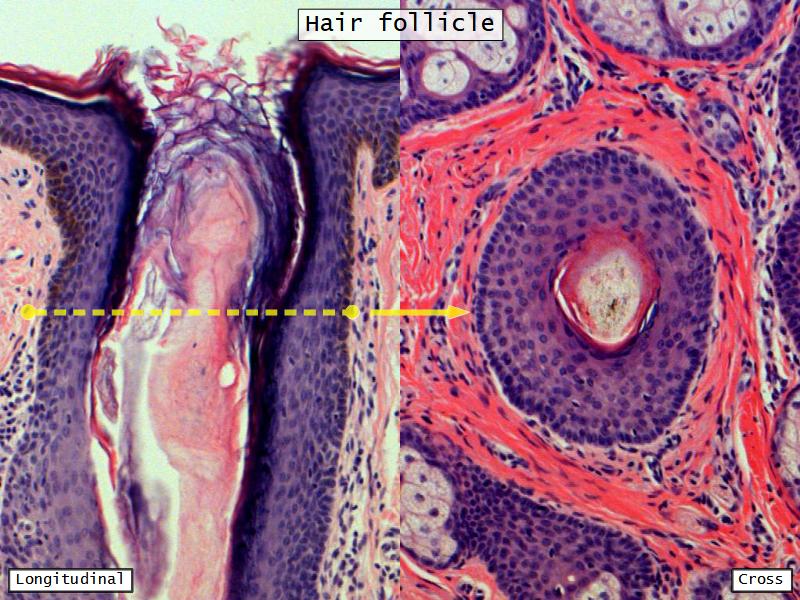

Slides: Respiratory System

- Slide 71: Nostril

Nostril